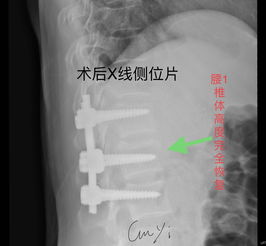

胸腰椎前路內(nèi)固定技術(shù)的應(yīng)用使病灶得到清除、脊髓獲得減壓、脊柱得到即刻穩(wěn)定,這樣一方面為病人術(shù)后早期離床活動(dòng)、早期康復(fù)提供了可能性,另一方面也為神經(jīng)功能的保護(hù)或恢復(fù)創(chuàng)造了必要條件;其合理性和臨床效果逐步得到了公認(rèn)。 但前路手術(shù)無(wú)法探查脊髓、馬尾損傷的情況并給于必要的處理,因此把握好前路手術(shù)的適應(yīng)證是臨床取效的關(guān)鍵,以下幾點(diǎn)基本達(dá)成共識(shí):胸腰椎骨折或骨折脫位伴不全癱,確證在硬脊膜前方有壓迫存在;經(jīng)過(guò)脊髓造影、MRI或臨床神經(jīng)學(xué)體征可判斷,除硬膜前受壓外,馬尾、脊髓本身并無(wú)需探查及修復(fù)時(shí),必須致力于前路減壓;脫位已超過(guò)2~3周者,后路手術(shù)已難以復(fù)位者;若伴不全癱需行減壓術(shù),亦宜選用前路減壓。

手術(shù)大致分為后路、側(cè)路、前路3個(gè)途徑。以往的手術(shù)常選擇后路的椎板減壓、探查+內(nèi)固定,但后來(lái)逐步發(fā)現(xiàn)后路手術(shù)在很多情況下難以恢復(fù)脊柱的正常形態(tài)及穩(wěn)定性,對(duì)來(lái)自前方的壓迫不易解除,長(zhǎng)期隨訪又發(fā)現(xiàn)了內(nèi)固定失效、融合失敗、脊柱不穩(wěn)、畸形愈合等情況;而且脊柱的后路內(nèi)固定術(shù)須通過(guò)前柱的承重來(lái)實(shí)現(xiàn)其張力帶作用,抵抗?fàn)繌埩蛷澢兀虼?,前方支撐系統(tǒng)不可或缺。